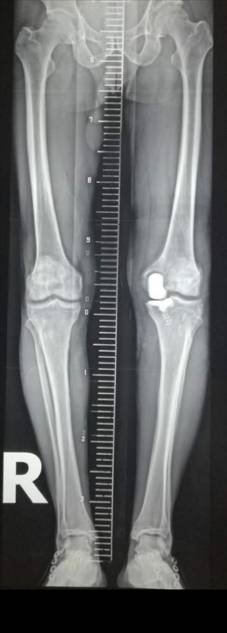

全髋关节置换术治疗股骨头坏死

优点:手术成熟,疗效确切。

术前术后对比

全髋关节翻修术